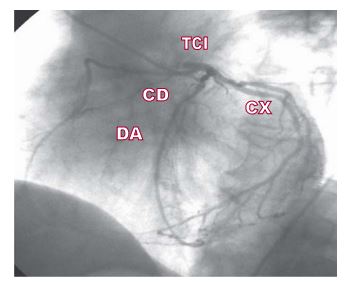

Nacimiento anómalo de la arteria coronaria derecha a partir de la descendente anterior

IMÁGENES EN CARDIOLOGÍA